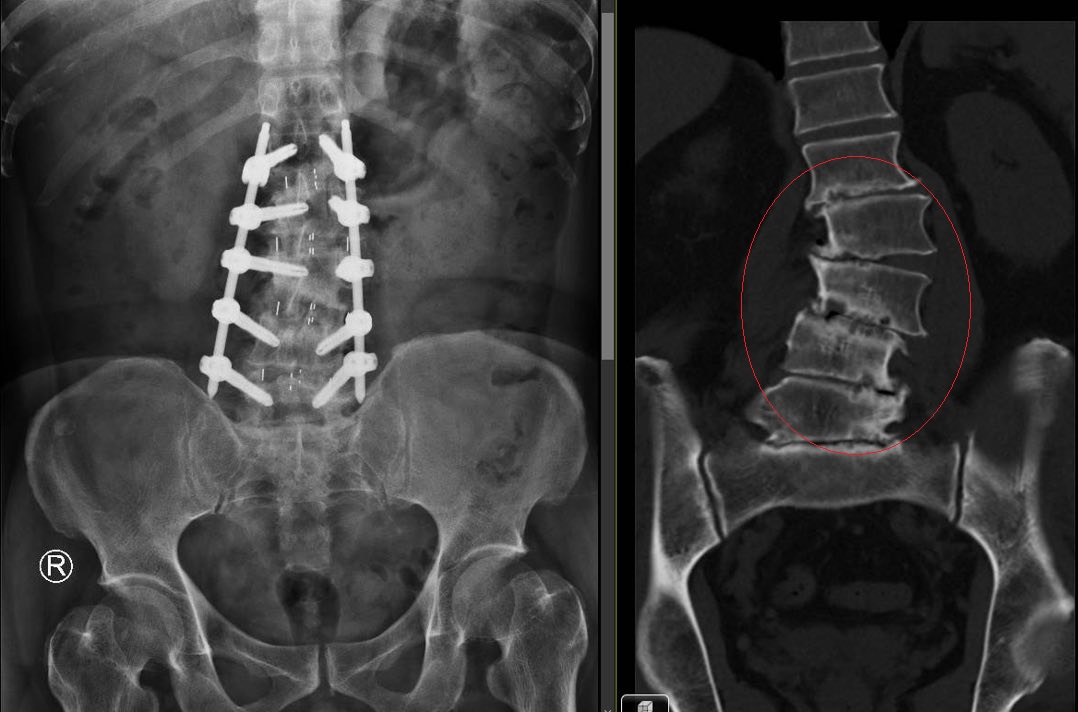

圖:胡先生第1至第5節腰椎的椎間盤嚴重磨損退化(右)/部立彰化醫院提供

陳柏辰表示,經影像檢查發現,胡先生第1至第5節腰椎的椎間盤已嚴重磨損退化,磨到扁平,導致脊椎側彎與滑脫,這正是長年背痛、無法多走路的病灶根源。

陳柏辰醫師表示,他為胡先生進行新式脊椎微創手術(OLIF),除了清除受損的椎間盤,並植入高分子聚合物的「斜位融合支架」,支撐力是傳統支架的3至5倍,穩固地將萎縮的椎間盤空間撐開,再配合骨釘植入,成功矯治了胡先生的脊椎側彎。